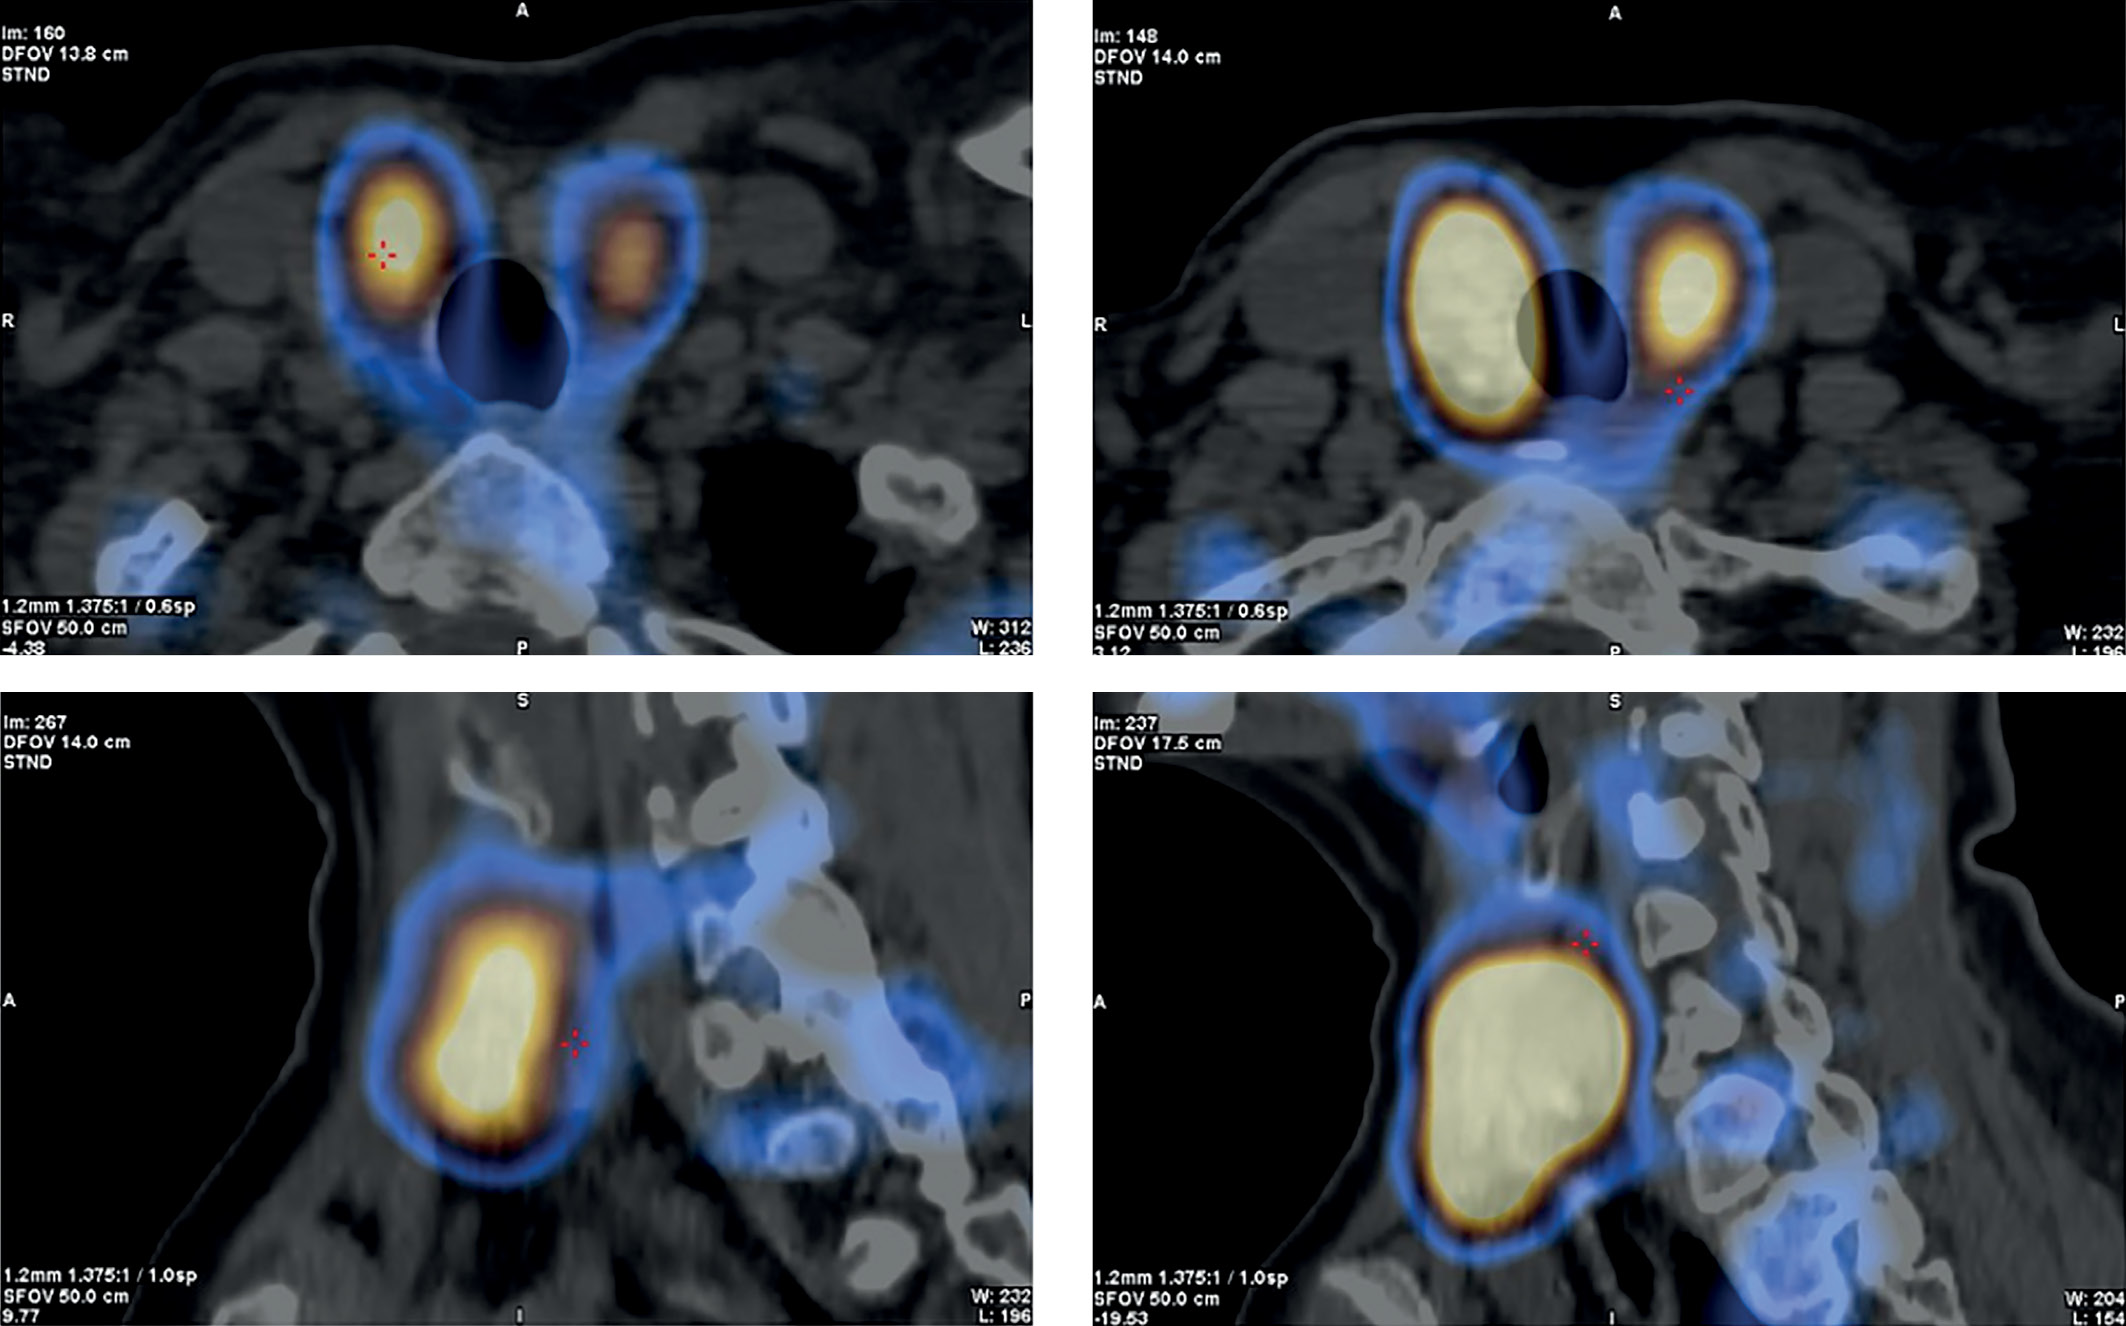

2. Рисунок 2. Сцинтиграфия околощитовидных желез с ОФЭКТ-КТ. | |